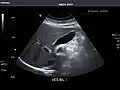

Abdominal ultrasound can be used to diagnose abnormalities in various internal organs, such as the kidneys,[1] liver, gallbladder, pancreas, spleen and abdominal aorta. If Doppler ultrasonography is added, the blood flow inside blood vessels can be evaluated as well (for example, to look for renal artery stenosis). It is commonly used to examine the uterus and fetus during pregnancy; this is called obstetric ultrasonography.[2][3]

Gallbladder: No stones, wall thickening, or pericholecystic fluid.

Common Bile Duct: Nondilated measuring 1.3 mm at the level of the porta hepatis.

Gallbladder -

Bile duct -

Gallbladder